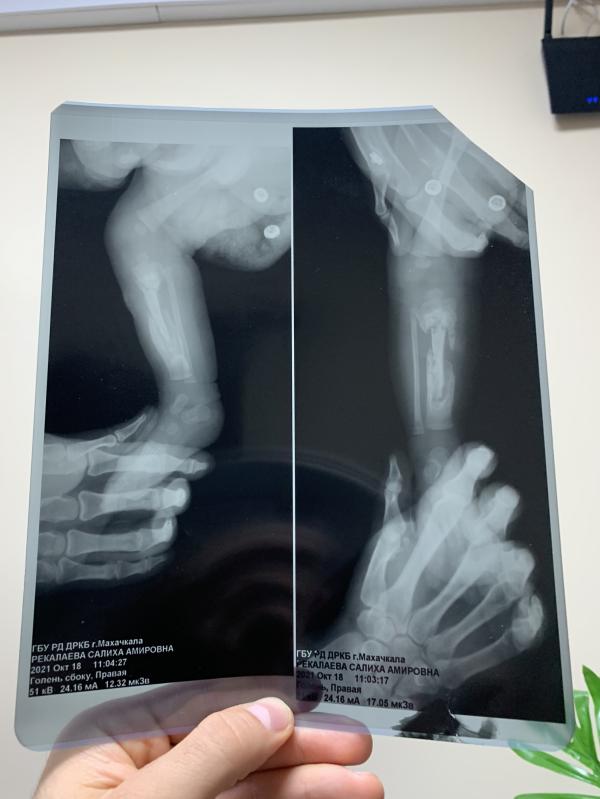

На утро, в день Х, заходит М.А в 7 утра, человек который раньше обеда не появлялся в палатах, ни на обход, ни вообще, а тут пришёл и со словами «Рекалаевы, вы остаётесь, у вас ужасная картина» зашёл. Знаете, я даже не удивилась, но у меня весь мир рухнул, я еле выдала «что не так?» он мне объясняет, на словах, я говорю «покажите снимок»(так как понимаю их), он показывает и я просто опустив голову начинаю тихо плакать, и на фоне слышу как он говорит «кость как сахарная раскрошилась, не знаю почему так, но оставлю вас ещё на пару недель, я ухожу в отпуск, передаю вас М.Т»